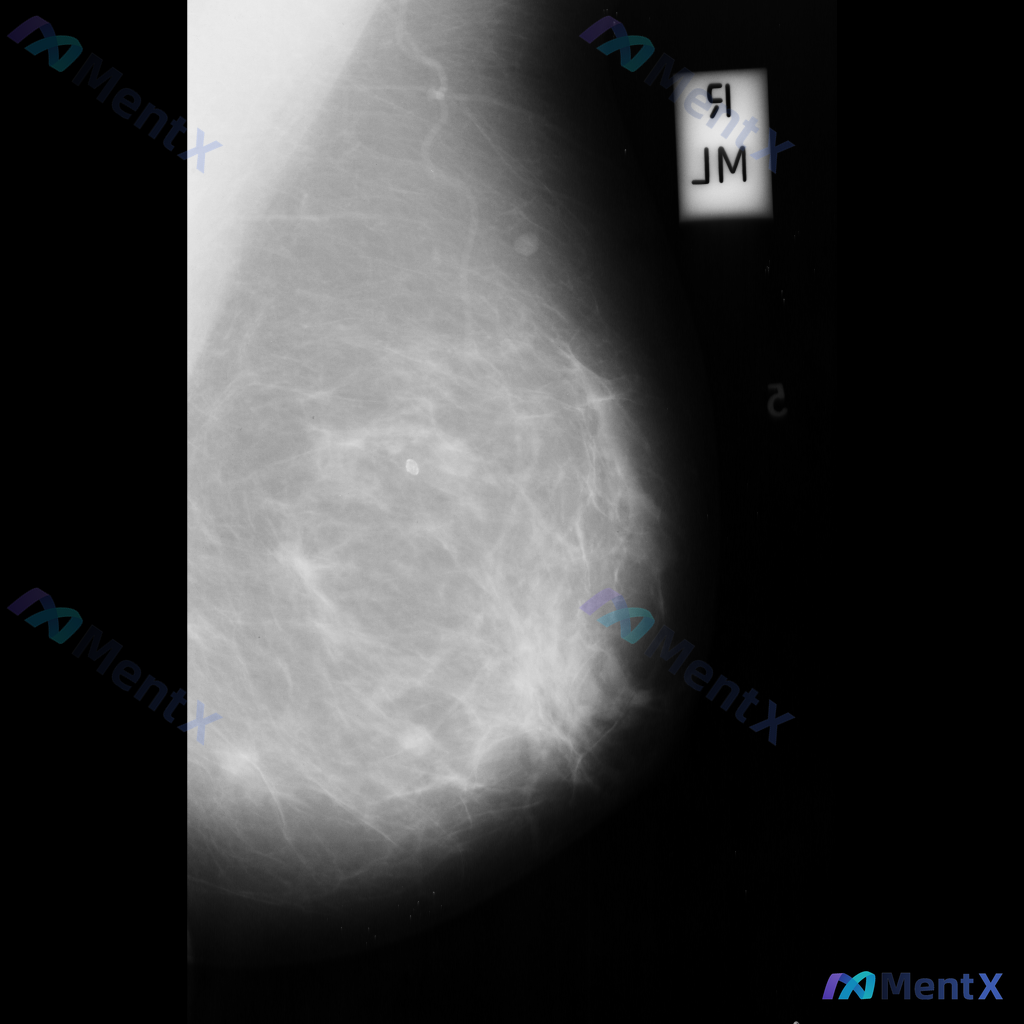

整理了一个乳腺钼靶读片的病例资料,大家可以一起讨论下性质判断的思路: 影像表现描述大致如下: - 乳腺中央偏上区域:可见不规则高密度影,密度较高,内部伴有粗大钙化,边缘不完全清晰; - 乳腺上部:可见类圆形高密度影,密度较高,边缘尚清晰但局部可能模糊; - 乳腺中部:可见数个散在的圆形或卵圆形结节影...

整理到一张乳腺钼靶影像的读片资料,分享给大家讨论。 影像表现:左乳中上象限可见一不规则形高密度致密影,边界部分模糊;内部可见细小、簇状分布的钙化影;同时局部乳腺腺体结构有轻度扭曲和牵拉。 目前需要判断的是,这组表现更支持哪一类情况?

整理到一张乳腺钼靶影像资料,影像所见:左乳中上象限可见不规则高密度致密影,边界部分模糊或伴毛刺状改变,局部乳腺组织结构可见轻度扭曲。 想和大家讨论一下:单看这张影像的异常表现,你认为用哪个术语描述最贴切?